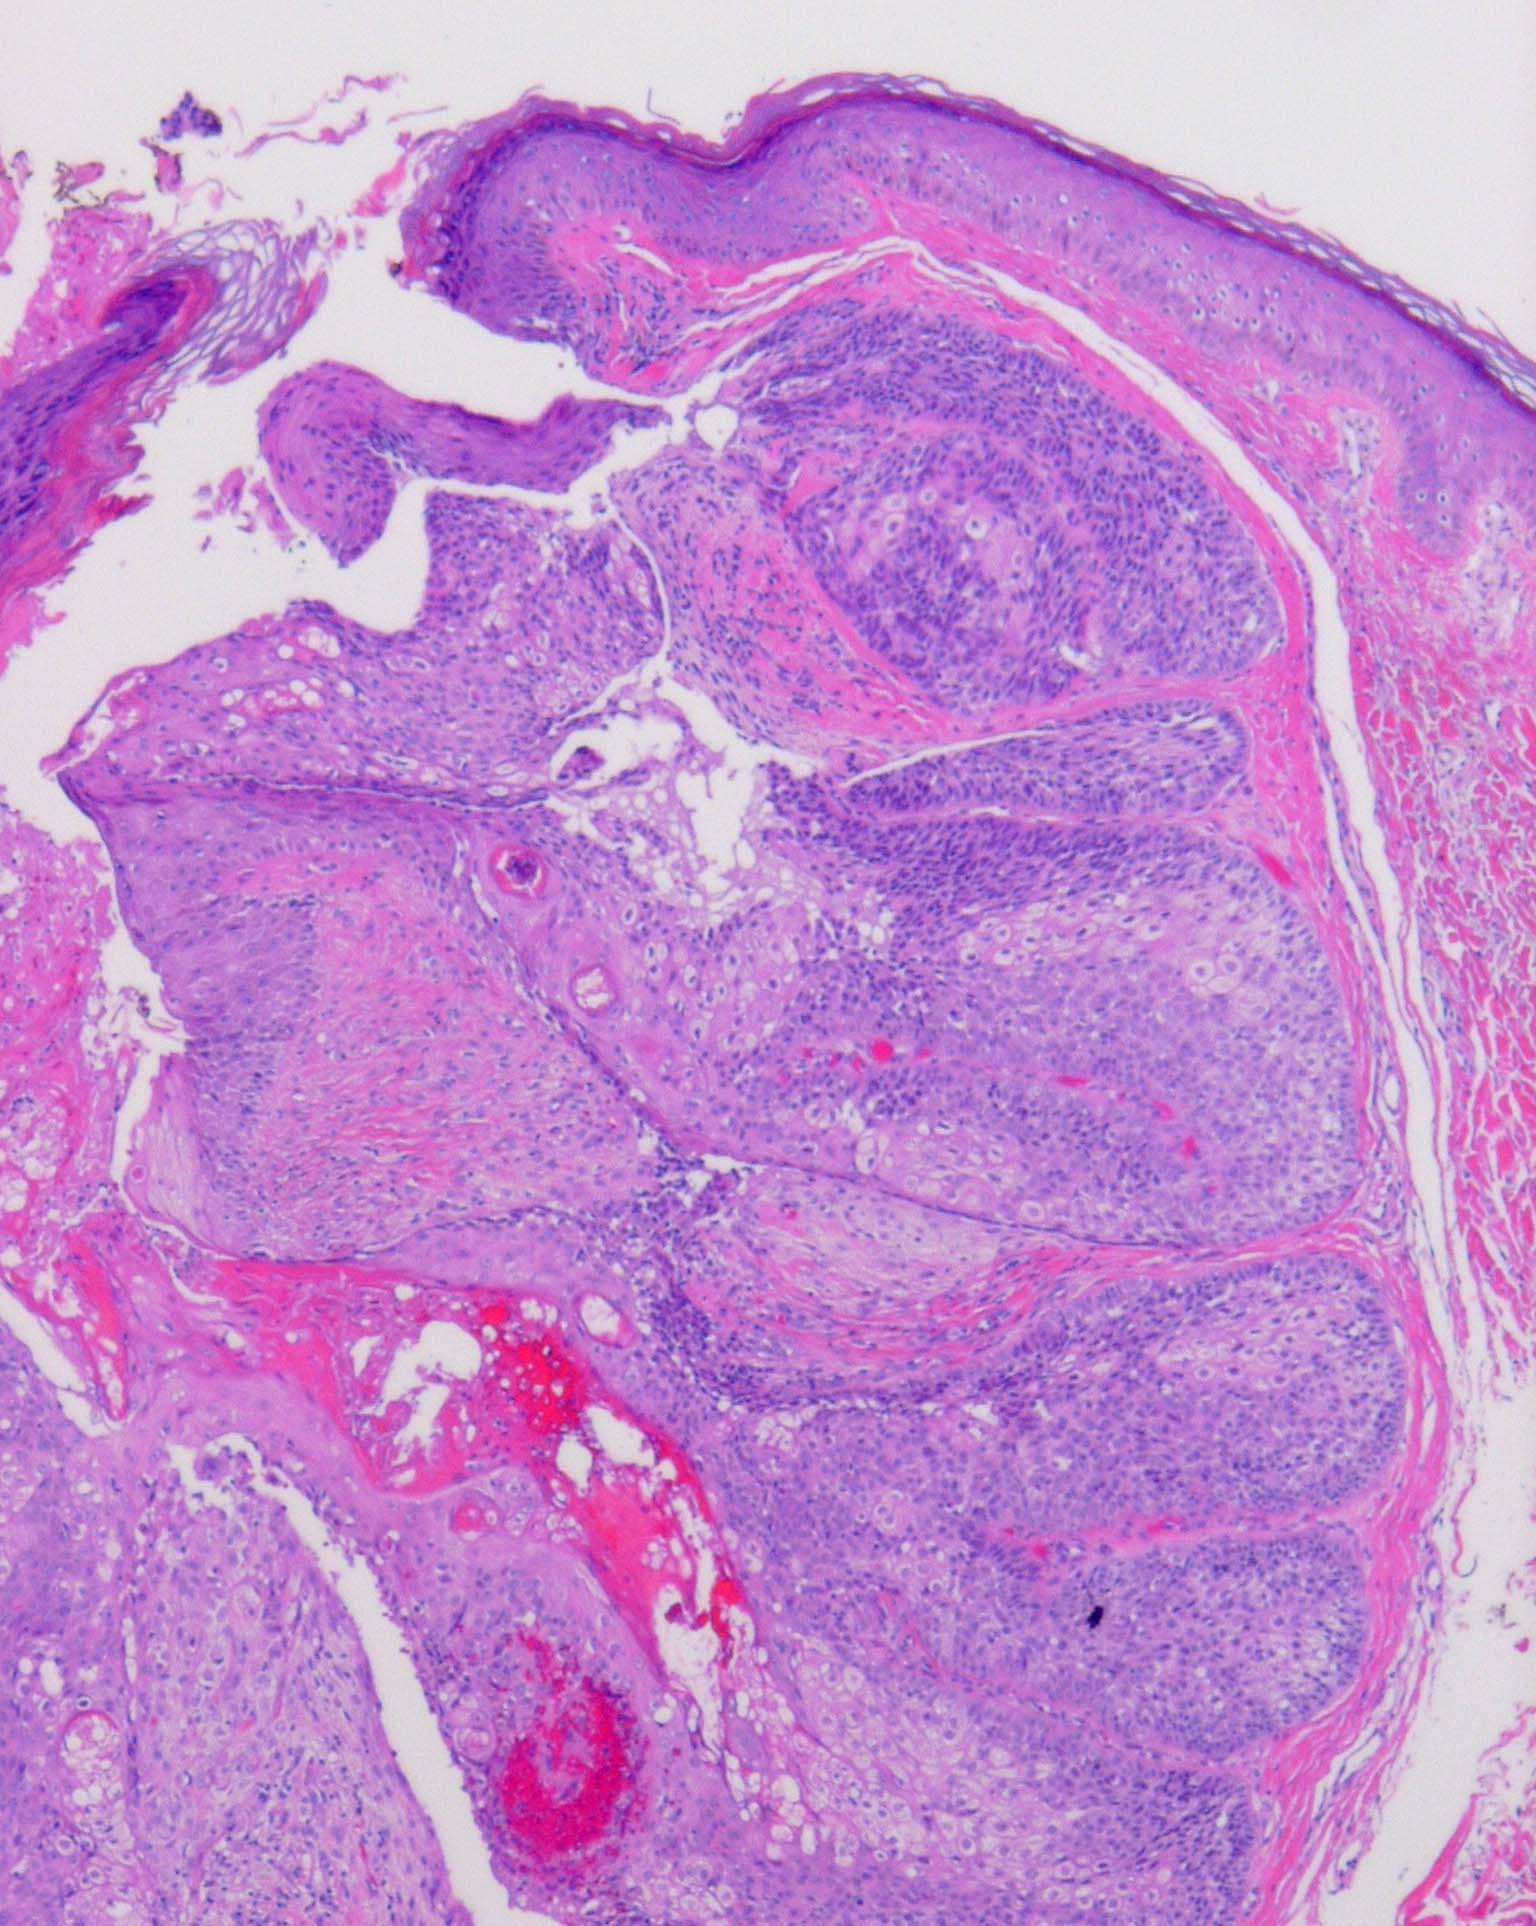

Sebaceous adenoma = غدوم دهني